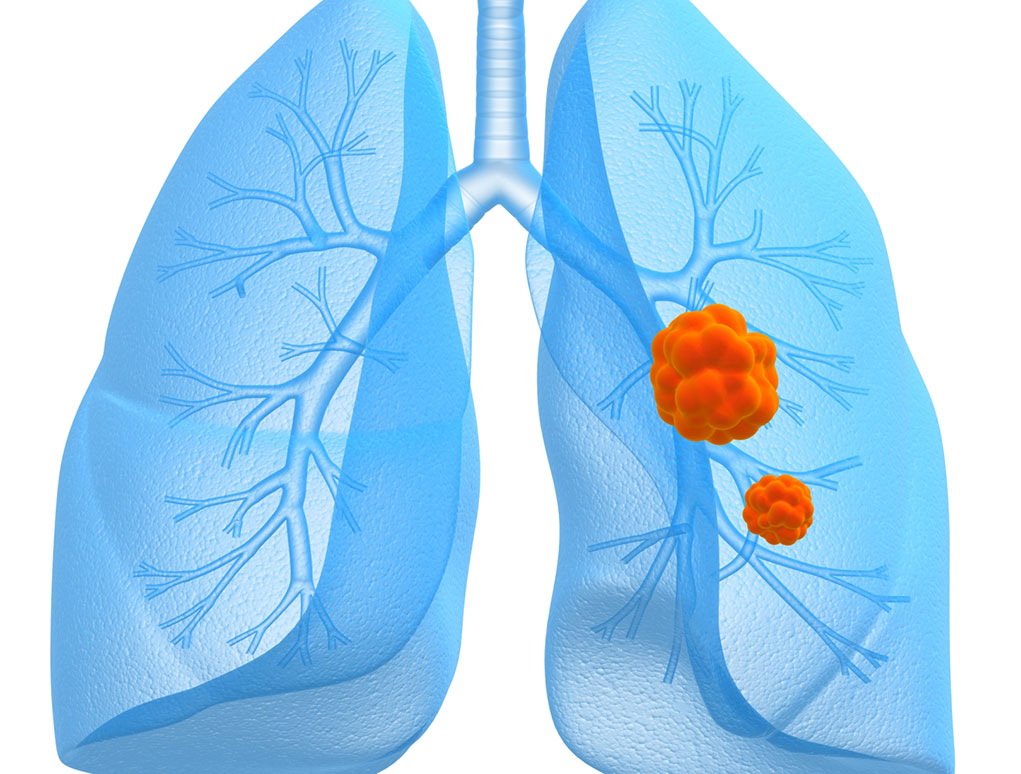

Пневмония - это серьезное заболевание легких, которое может быть вызвано различными причинами, включая бактериальные, вирусные и грибковые инфекции. Для того чтобы наглядно показать симптомы, диагностику и лечение этого заболевания, картинки могут быть очень полезны.

Картинки с симптомами пневмонии

В этом разделе представлены изображения, демонстрирующие различные симптомы пневмонии, такие как кашель, одышка, боль в груди и повышенная температура. Эти картинки могут быть использованы для обучения и презентаций в области медицины и здравоохранения.